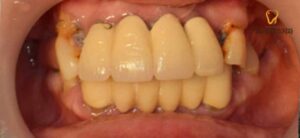

틀니가 마무리되고 난 후에는

하악 전치부 브릿지를 상악 틀니의 교합에 맞춰

소구치까지 연결하여 제작하였고,

3달 정도의 시간이 지나 치조골과

픽스쳐가 단단히 유착되어

함께 보철물 제작을 진행하였습니다.

환자분께서는 임시 틀니에 비해

불편함이 없고 생각보다 강한 유지력에 만족해하셨으며,

하악 임플란트와 브릿지,

틀니 모두 심미적으로 만족스럽고

교합이 잘되어 식사가 편해지셨다며

감사의 인사를 건네주셨습니다.